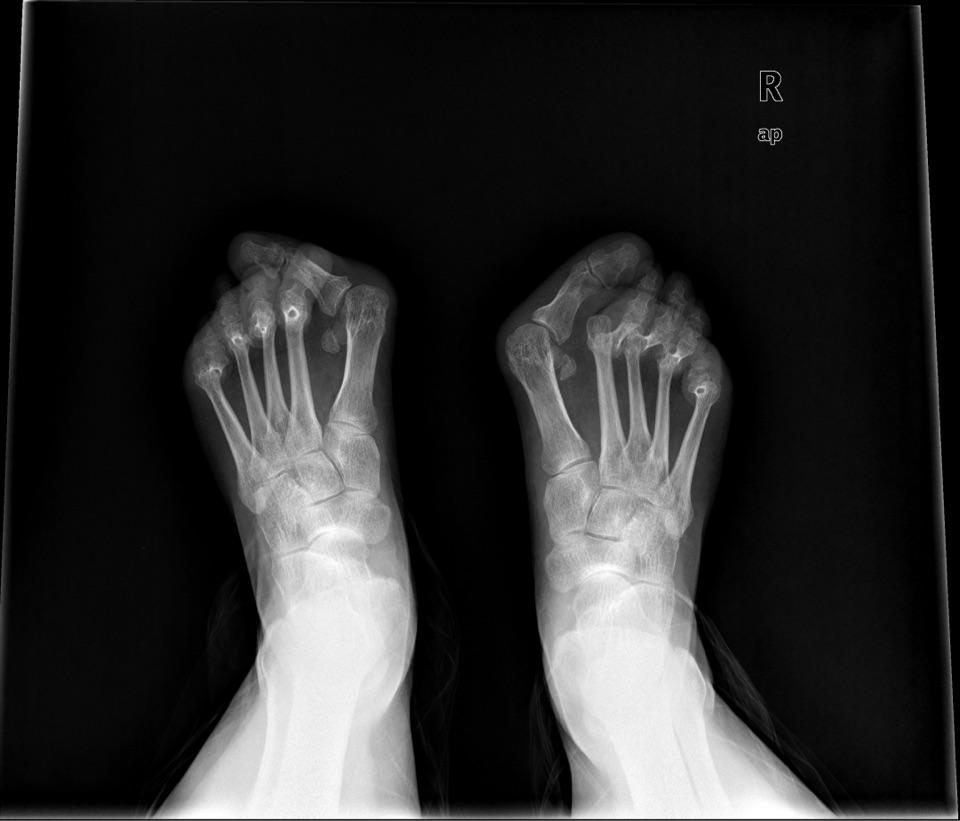

中山男子20年没有合穿的鞋子,原因很罕见

踇外翻——对女性造成困扰最大的足部畸形_刘津浩医生

濮阳三院骨科——给我一双美丽的脚